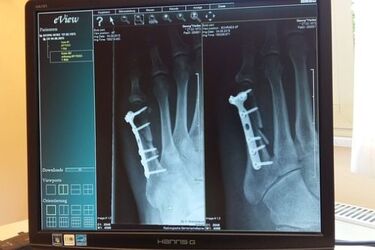

Jedną z najnowszych metod leczenia dysfunkcji narządu ruchu jest wykorzystanie krwi pacjenta, a dokładnie jej składowej - osocza, z którego uzyskuje się osocze bogatopłytkowe PRP (z ang. Platelet Rich Plasma). Lekarze na całym świecie używają PRP do leczenia urazów stawów i uszkodzeń tkanek miękkich, podczas gojenia złamań kości, w tym przede wszystkim przy zaburzeniach zrostu kostnego. Metodę tę zaczęto też szeroko stosować w leczeniu chorób zwyrodnieniowych stawów (kolanowych, biodrowych, barkowych).

Od pacjenta pobiera się krew i w procesie odwirowywania otrzymuje się jej różne frakcje. Uzyskiwane w ten sposób osocze bogatopłytkowe jest wstrzykiwane w okolicę wymagającą regeneracji. Zabieg może być wykonywany pod kontrolą USG oraz w znieczuleniu i zwykle jest jednorazowy. Trwa kwadrans. Z kolei efektów chory może spodziewać się po kilku tygodniach. Przy czym powrót do zdrowia znacznie przyspiesza rehabilitacja.